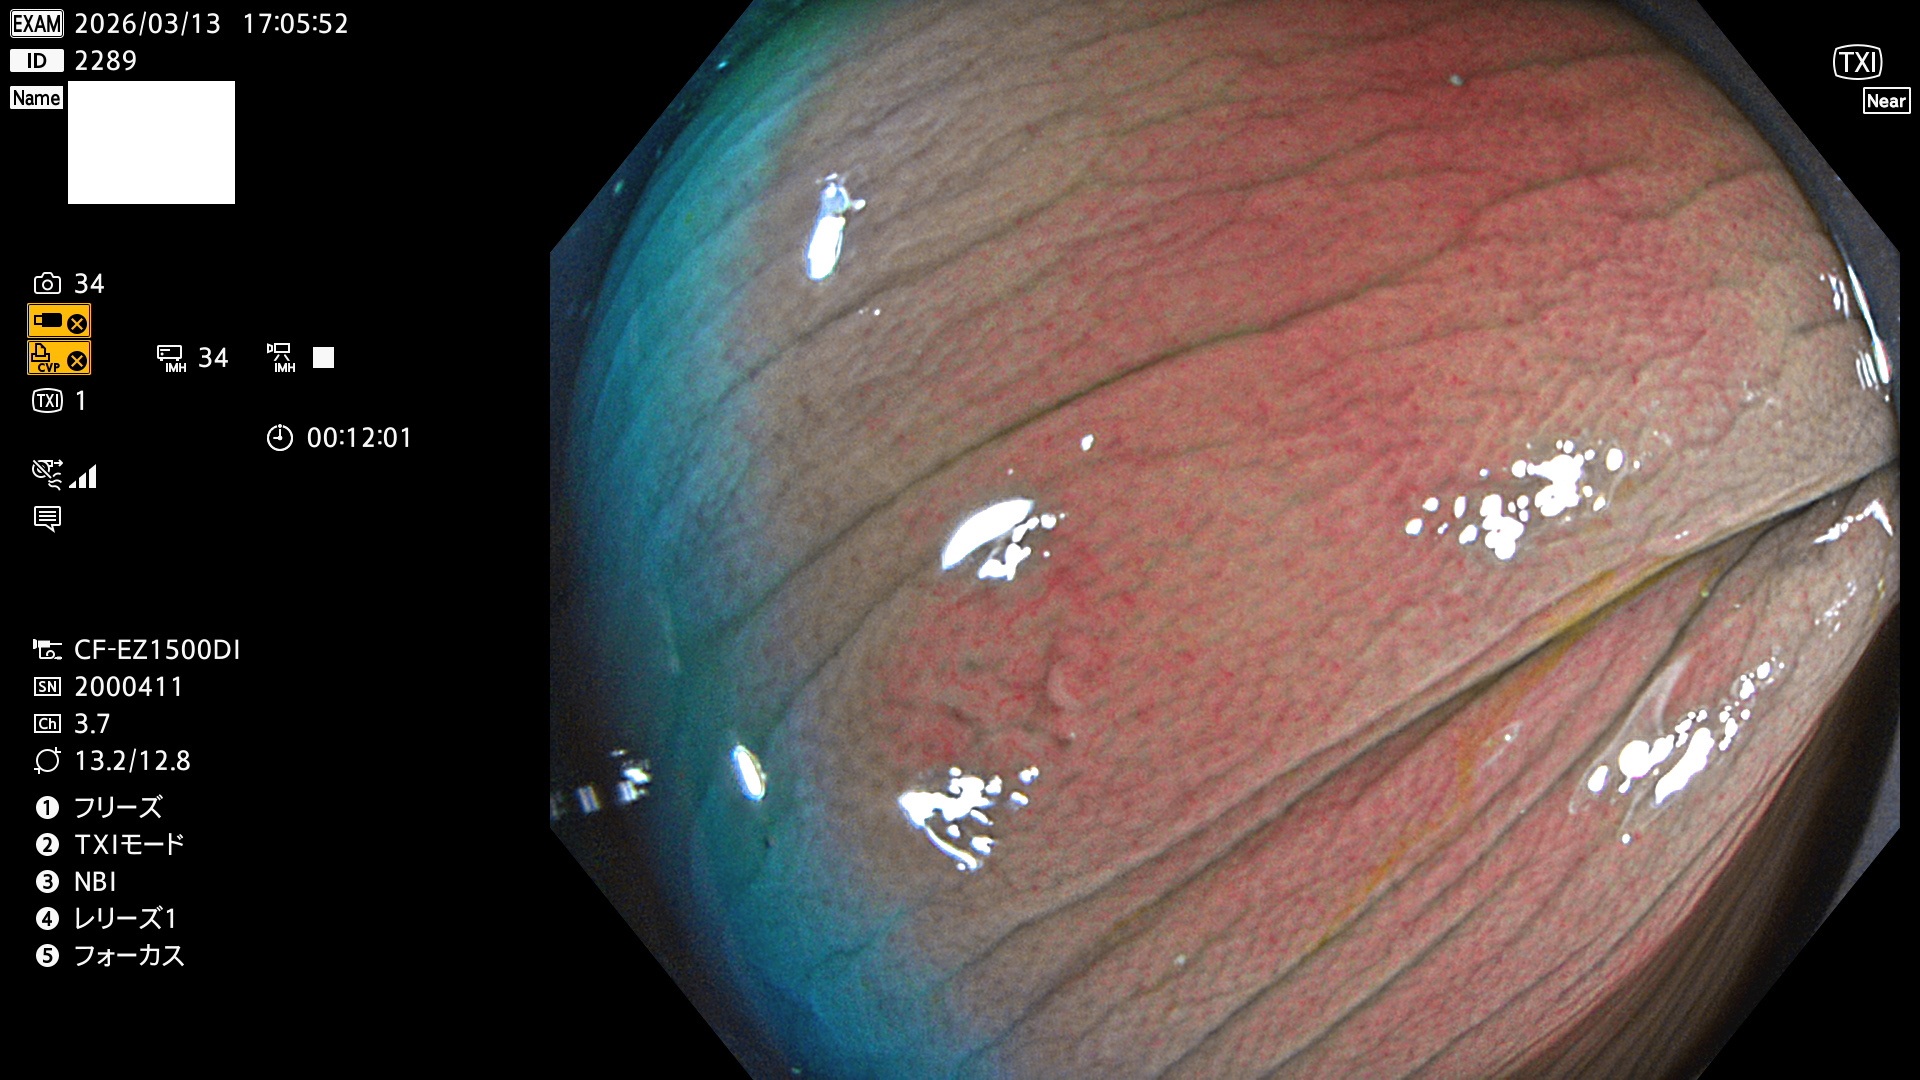

毎週の検査(木・金・土・日)に発見されたUbとUc型・腺腫を、その週の日曜の夜にUPし1週間、提示します。

2026年3月12日〜3月15日の4日間(40件)6個 (Uc_ADR=6個/40人=15%)